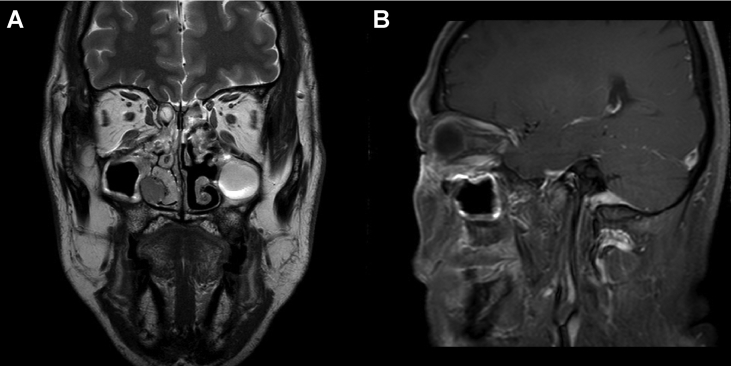

MRI with contrast enhancement showed a T2 intermediate enhancing mass extending from the right inferior extraconal space of the orbit to the right nasal cavity along the right nasolacrimal duct (Fig. 1). In-house computed tomography showed no significant interval change, but accentuated expansile bony change with destruction in the nasolacrimal duct when compared with MRI (Fig. 2). Positron emission tomography/computed tomography revealed no evidence of distant metastasis.

Fig. 1.

Magnetic resonance imaging with contrast enhancement, showing a T2 intermediate enhancing mass in the study patient. (A) The mass extended from the right inferior extraconal space of the orbit to the right nasal cavity along the right nasolacrimal duct (T2WI). (B) Invasion of the mass into the right inferior oblique muscle could be noted on T1WI.